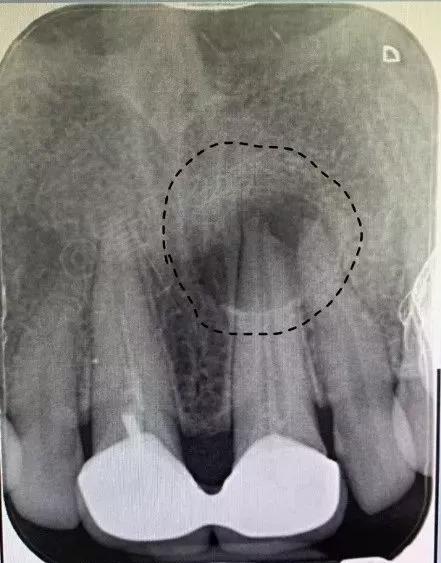

1.X光检查。X光片可看到龋坏的范围、根尖周围的病变,以及曾经做过的治疗情况。复杂的病例可能还需拍摄锥形束CT来帮助诊断。下图的根尖X光片可以看到曾经牙齿的根管填充不足(可在后文对比图中看出),以及牙齿根尖处的病变(黑色虚线圈出的圆形阴影)。

可看到根尖周围的病变,以及曾经做过的(不合格)的根管治疗

下图是一位患者治疗的前后对比。右图为治疗后2个月,可以看到阴影区域颜色明显变浅,证明感染愈合,牙槽骨正在形成。

治疗前(左)后(右)对比